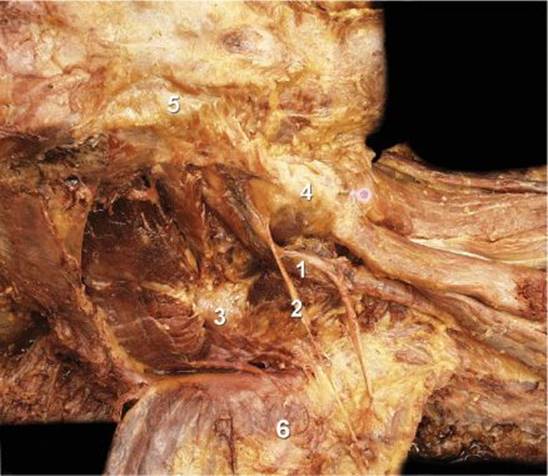

The sciatic nerve exits the pelvis through the greater sciatic foramen below the piriformis and descends between the greater trochanter of the femur and the ischial tuberosity, superficial to the external rotators of the hip (obturator internus, the gemelli muscles, and quadratus femoris) (Figures 19.1-2 and 19.1-3). On its medial side, the sciatic nerve is accompanied by the posterior cutaneous nerve of the thigh and the inferior gluteal artery. The articular branches of the sciatic nerve arise from the upper part of the nerve and supply the hip joint by perforating the posterior part of its capsule. Occasionally, these branches are derived directly from the sacral plexus. The muscular branches of the sciatic nerve are distributed to the biceps femoris, semitendinosus, and semimembranosus muscles, and to the ischial head of the adductor magnus. The two components of the nerve (tibial and common peroneal) diverge approximately 4 to 10 cm above the popliteal crease to separately continue their paths into the lower leg.

FIGURE 19.1-3. Anatomy of the sciatic nerve at the subgluteal location.

sciatic nerve.

nerve branch to the gluteus muscle.

ischial bone.

greater trochanter.

posterior superior iliac spine.

gluteus muscle.